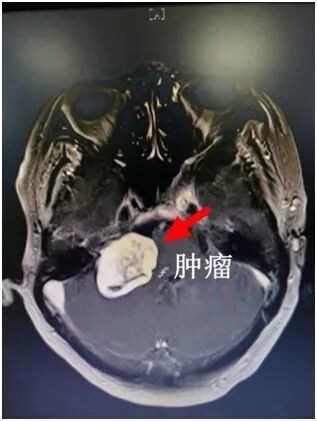

2019年的10月,70歲的劉奶奶因肢體感覺無力、聽力下降等癥狀,慕名來到惠州市第三人民醫(yī)院神經(jīng)外科,找到了李雪松博士。經(jīng)過檢查,醫(yī)生發(fā)現(xiàn)患者顱內(nèi)右側(cè)橋小腦角區(qū)有一個巨大腫瘤,初步判斷是聽神經(jīng)瘤。

“如果不及時干預(yù),隨著腫瘤越來越大,患者可能會出現(xiàn)一側(cè)聽力完全喪失,肢體癱瘓甚至危及生命的發(fā)生……”當(dāng)時,李雪松博士為患者及家屬詳細(xì)講解了病情和治療手段。他和藹可親的樣子給患者及家屬留下了深刻的印象,也仿佛給他們吃下了一顆“定心丸”。

2019年李雪松醫(yī)生為患者手術(shù)

后來,李雪松博士團隊在多科協(xié)作下共同為患者制定了詳細(xì)手術(shù)治療方案,最終克服患者年齡大、腫瘤復(fù)雜等困難,經(jīng)過6小時的不懈努力,順利將腫瘤全切。術(shù)后,患者恢復(fù)良好且未出現(xiàn)并發(fā)癥,肢體活動正常,聽力也漸漸好轉(zhuǎn)起來。對此,患者和家屬都感到非常滿意,對李雪松博士及醫(yī)護團隊的精心治療和照顧十分感激。